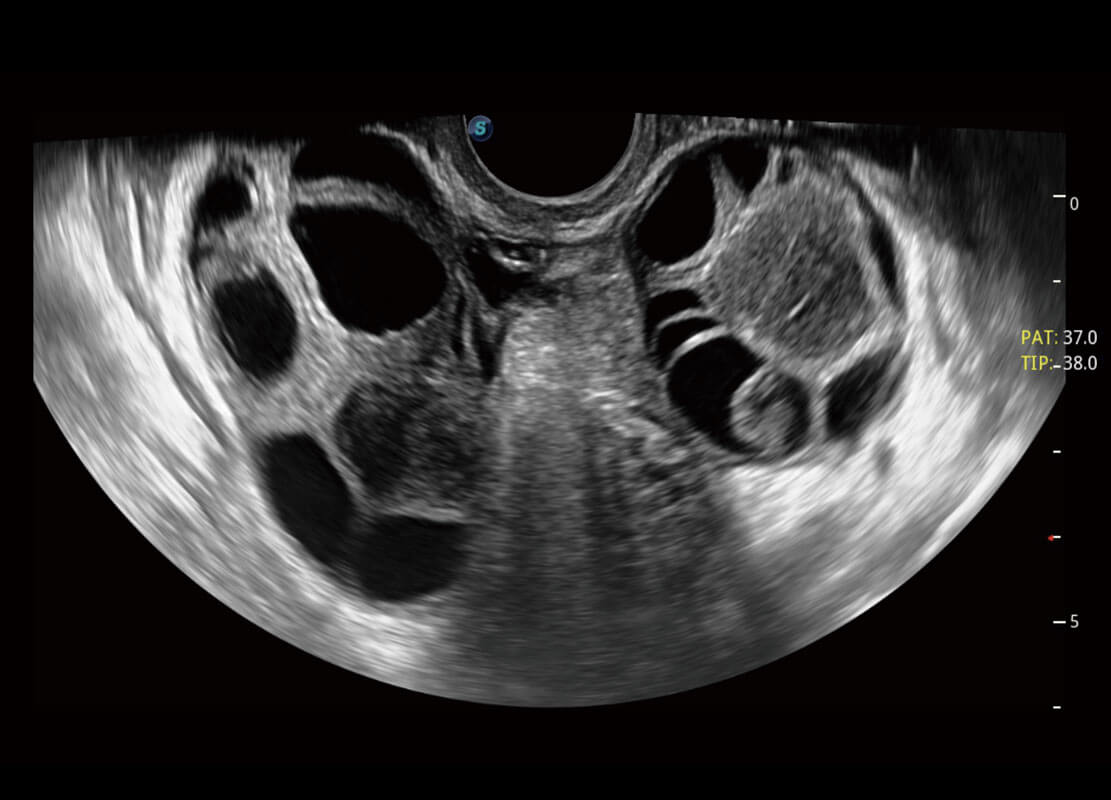

P60优异的图像质量搭载专科探头,在妇科基础疾病的诊断、卵泡生长的监测、输卵管通畅情况的判别等方面为您提供生殖应用方案。

腔内妇科-卵巢